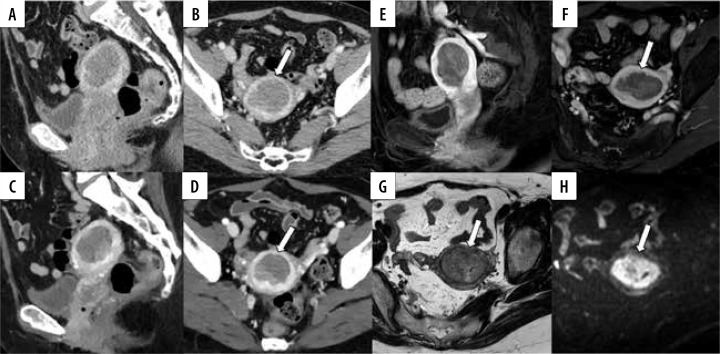

Material and methods: This retrospective study analysed 45 EC patients (mean age: 62 years, range: 44-84 years) undergoing contrast-enhanced CT with dual-energy CT (DECT) and MRI between September 2021 and October 2022. Dual-energy CT generated conventional CT (C-CT) and 40 keV VMI. Quantitative analysis compared contrast-to-noise ratio (CNR) of tumour to myometrium between C-CT and VMI. Qualitative assessment by 5 radiologists compared C-CT, VMI, and MRI for myometrial invasion (MI), cervical invasion, and lymph node metastasis. Sensitivity, specificity, accuracy, and area under the receiver operating characteristic curve (AUC) were calculated and compared for each diagnostic parameter.

Results: Virtual monoenergetic imaging showed significantly higher CNR than C-CT (p < 0.001) and a higher sensitivity for MI than C-CT (p = 0.027) and MRI (p = 0.011) but lower specificity than MRI (p = 0.018). C-CT had a higher sensitivity and AUC for cervical invasion than MRI (p = 0.018 and 0.004, respectively).

Conclusions: The study found no significant superiority of MRI over CT across all diagnostic parameters. VMI demonstrated heightened sensitivity for MI, and C-CT showed greater sensitivity and AUC for cervical invasion than MRI. This suggests that combining VMI with C-CT holds promise as a comprehensive preoperative staging tool for EC when MRI cannot be performed.